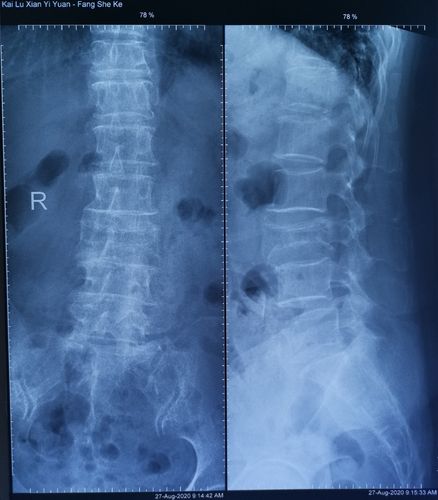

腰椎正侧位x光片:可见腰1椎体压缩性骨折 上终板塌陷,椎体前缘骨折块

腰椎压缩性骨折平片